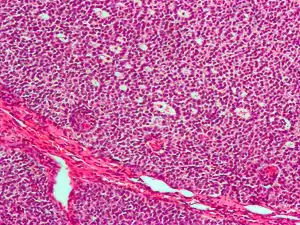

| Micrograph of a granulosa cell tumour, a type of sex-cord–gonadal stromal tumour. H&E stain. | |